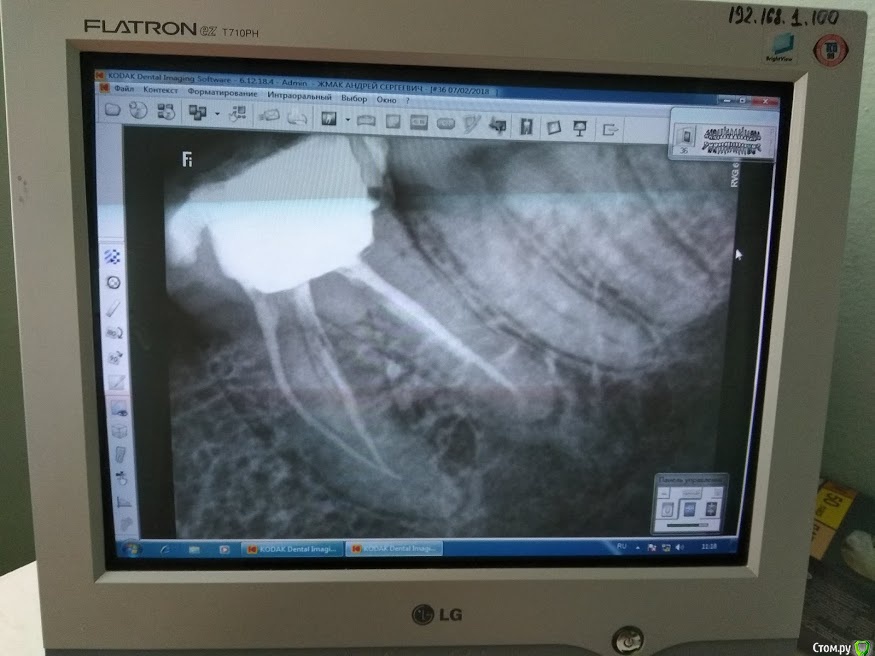

Anzh Опубликовано 20 февраля, 2018 Поделиться Опубликовано 20 февраля, 2018 Здравствуйте! В октябре были удалены нервы из зуба, но через месяц зуб начал болеть при надавливании и отдавать в ухо, также периодически зуб болел и даже без надавливания. Стоматолог вновь прочистил каналы и заново запломбировал, но это не помогло. Был сделан вот этот снимок. После этого зуб был опять распломбирован, туда стоматолог вставлял какое-то лекарство, делал уколы антибиотиков в десну, но зуб так и болит при надавливании и периодически и без надавливания, отдает иногда в ухо. Сейчас стоматолог все лекарства убрал из зуба и сказал походить пока так с открытым. В открытом состоянии зуб не болит, только есть небольшая боль, когда постукиваешь по тому краю, который ближе к дырке от удаленного зуба. Стоматолог сказал, что не понимает в чём проблема и скорее всего если через неделю зуб не перестанет болеть, то придется его удалить. Прошу помощи. Ссылка на комментарий

АнтонТЛТ Опубликовано 20 февраля, 2018 Поделиться Опубликовано 20 февраля, 2018 Здравствуйте. Корневые каналы обработаны не на всю длину. Зуб нуждается в перелечивании у эндодонтиста, в идеале работающим с использованием операционного микроскопа. Ссылка на комментарий